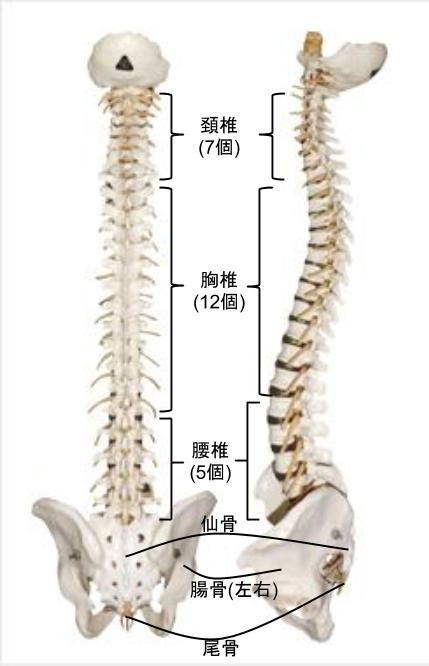

昨年の10月から週に1回のペースでアジャストメントを行ってきました。アジャストメントを行った箇所は、骨盤(腸骨や仙骨)、第6胸椎(T6)から第9胸椎(T9)、第7頚椎(C7)が中心でした。

脊柱解剖学(Spinal Anatomy)